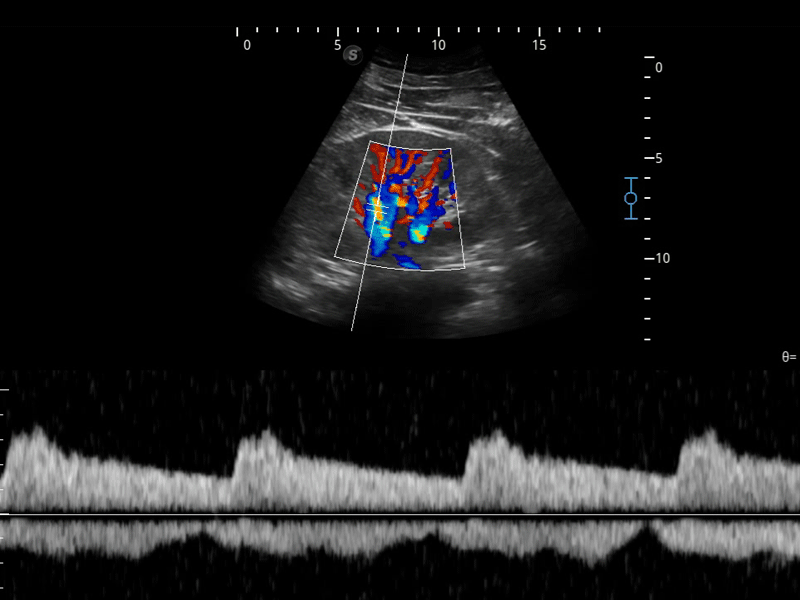

開立醫(yī)療通過不斷的技術(shù)創(chuàng)新,為大眾的生命健康提供持續(xù)關(guān)愛。P12 Plus采用全新一代超聲成像平臺(tái),新平臺(tái)旨在將真實(shí)還原組織解剖結(jié)構(gòu)作為首要目標(biāo)。平臺(tái)采用全新集成化硬件模塊,搭載新一代芯片,系統(tǒng)性能得到大幅提升,為您的診斷提供了豐富的臨床信息。優(yōu)異的圖像表現(xiàn),豐富的探頭配置,全面的應(yīng)用功能,為您日常診斷提供了可靠的助手。

彩色多普勒超聲診斷系統(tǒng)